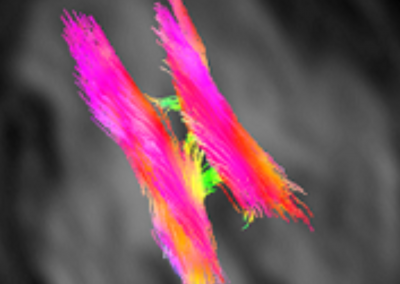

L’Université Paris Cité franchit une nouvelle étape dans le domaine de l’imagerie médicale anténatale avec l’acquisition d’un système d’Imagerie par Résonance Magnétique (IRM) 1,5T ARTIST™ de GE HealthCare. Cet équipement de pointe renforce les capacités de la Plateforme LUMIERE à l’hôpital Necker-Enfants malades, plateforme intégrée de soins, de recherche clinique et d’enseignement en imagerie médicale de la femme enceinte, du fœtus et du placenta.

Une avancée technologique majeure pour la recherche anténatale

La Plateforme LUMIERE accueille chaque année plusieurs jeunes chercheurs (masters, doctorants et post-doctorants). Leurs travaux de recherche visent, à terme, à améliorer le diagnostic et le pronostic des pathologies anténatales, afin de mieux anticiper et optimiser la prise en charge des nouveau-nés. Ces travaux ont déjà mené à des communications et des publications scientifiques dans des revues à comité de lecture.